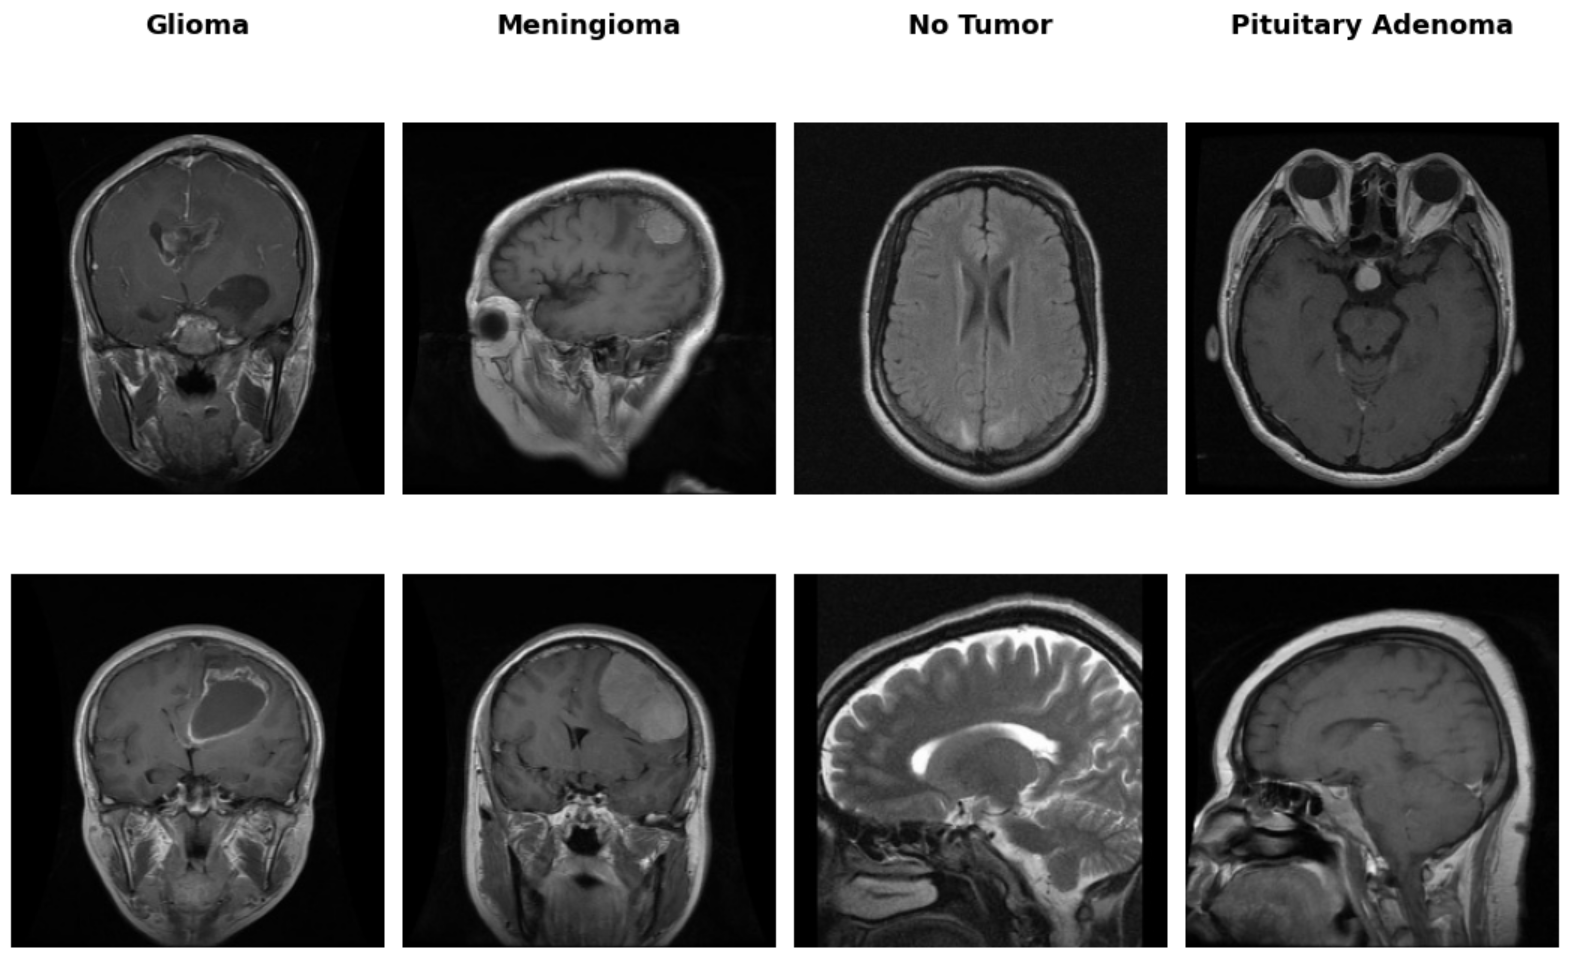

Following the augmentation assessment, we turned our attention to the integrity of the dataset itself—specifically the presence of duplicate images. During this phase of exploratory analysis, we identified a substantial number of duplicate instances, both within individual tumor classes (intra-class) (Figure 4: Image(70) & Image(71)) and, more concerningly, across different classes (inter-class) (Figure 4: Image(2) & Image(48)). In total, nearly 400 duplicates were detected, a subset of which appeared under conflicting class labels, suggesting possible mislabeling errors introduced during dataset curation.

The presence of duplicate images poses several challenges to model generalization. Intra-class duplicates can lead to data leakage between training and validation splits, inflating performance metrics and impairing real-world robustness. Inter-class duplicates are particularly detrimental, as they present the model with visually identical images assigned to different labels—confusing the learning process and eroding the consistency of decision boundaries. This is especially critical in clinical applications, where the reliability of model predictions must meet a high standard of diagnostic fidelity.

Examples of both intra- and inter-class duplication are shown below (Figure 4). Such anomalies necessitate rigorous preprocessing and data auditing pipelines prior to model training.

Figure 4: Examples of intra- and inter-class duplicates.

Data Duplicates